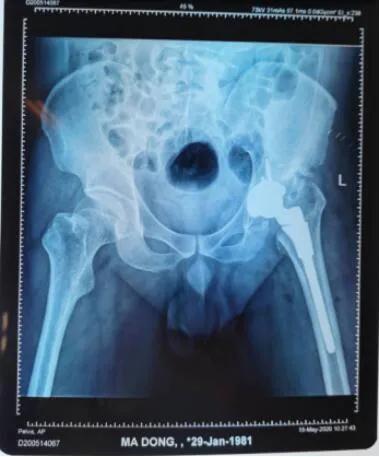

术后。

经过一系列检查,确诊为“左髋关节化脓性关节炎后遗症”,最佳的治疗方案是全髋关节置换术。

从拍摄的影像片看出,马先生左侧股骨头已基本消失并且明显上移,错位明显,已与“假”的髋臼形成“假”关节。

术前。

“术中需要为患者置换、重建一个新的髋关节。”操作本次手术的李璐兵医生说,手术最大的难点在于在周围都是重要血管神经的复杂环境下准确的定位找到“真臼“,然后在“真臼“上精准操作安装新的关节。